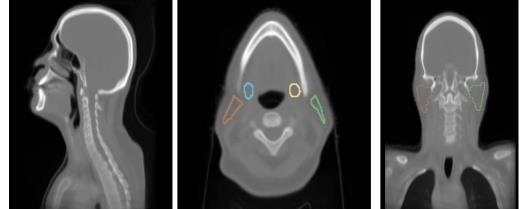

We develop an interpretable deep learning model for xerostomia prediction using anatomy normalization and high-resolution class activation maps for improved spatial interpretability.

Bohua Wan, T. McNutt, H. Quon, J. Lee

Proc. SPIE Medical Imaging 2025 (2025).

We propose a novel deep learning framework for predicting radiation-induced xerostomia using supervised contrastive pre-training and cluster-guided loss.

Bohua Wan, T. McNutt, R. Ger, H. Quon, J. Lee

Proc. SPIE Medical Imaging 2024 (2024).